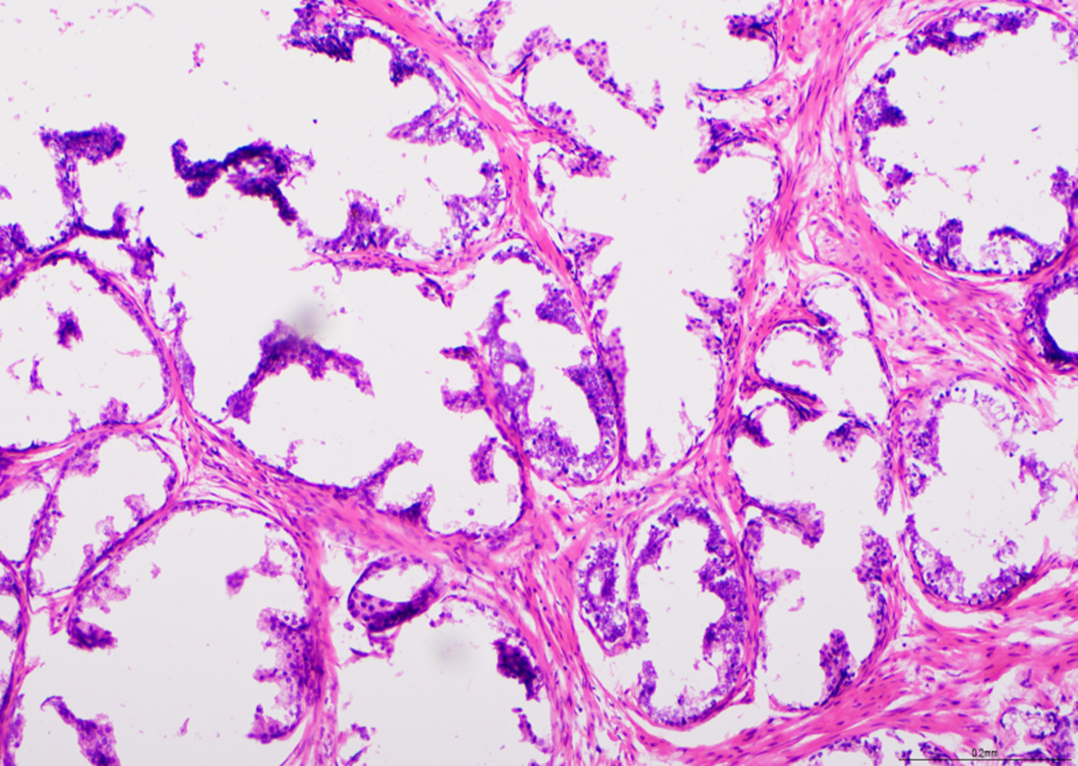

Tricromo de Gomori: músculo fresco

Este es un ejemplo de una preparación deficiente seguida de una tinción deficiente. Como ocurre con todos los métodos de tinción de músculo fresco, una buena preparación es fundamental. Si su laboratorio tiene dificultades, puede acceder a los Protocolos de Mejores Métodos y a evaluaciones adicionales de control de calidad. Esta prueba obtuvo una puntuación de 2/10.